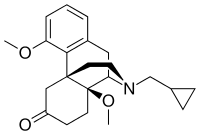

Others

- 1-Nitroaknadinine * 14-episinomenine

- 5,6-Dihydronorsalutaridine

- 6-Keto Nalbuphine

- Aknadinine

- Butorphanol

- Cephakicine

- Cephasamine

- Cyprodime

- Drotebanol

- Fenfangjine G

- Ketorfanol

- Nalbuphine

- Nalbuphone

- Tannagine

Structures

| Other Morphinans | ||||

|---|---|---|---|---|

1-Nitroaknadinine 1-Nitroaknadinine |

14-episinomenine 14-episinomenine |

5,6-Dihydronorsalutaridine 5,6-Dihydronorsalutaridine |

6-Keto Nalbuphine 6-Keto Nalbuphine |

Aknadinine Aknadinine |

Butorphanol Butorphanol |

Cephakicine Cephakicine |

Cephasamine Cephasamine |

Cyprodime Cyprodime |

Drotebanol Drotebanol |

Fenfangjine G Fenfangjine G |

Nalbuphine Nalbuphine |

Sinococuline Sinococuline |

Sinomenine Sinomenine |

Tannagine Tannagine |